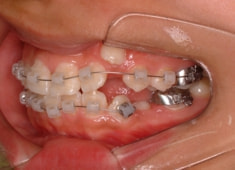

治療開始から5ヶ月後